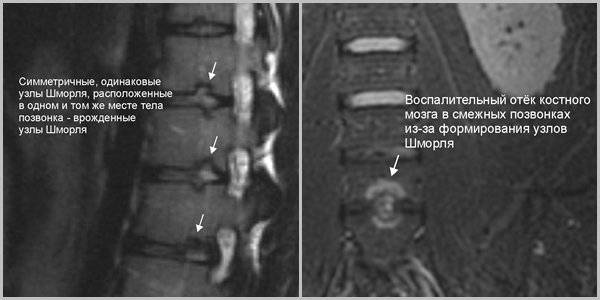

Мрт картина дегенеративно дистрофических изменений пояснично крестцового отдела позвоночника